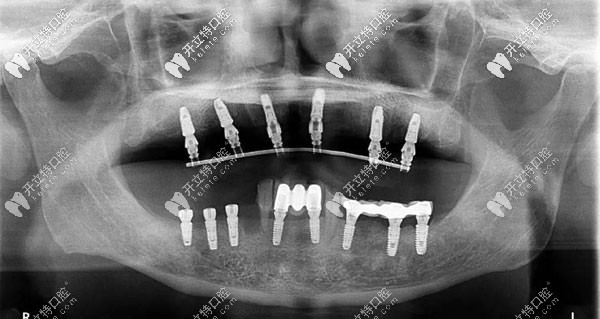

半口牙種植6或8顆植體全景圖

此外,all-on-6半口種植技術(shù),也就是種植6顆植體,配搭拱橋連冠,也是一個(gè)不錯(cuò)的選擇,還減輕了頜骨的負(fù)荷。